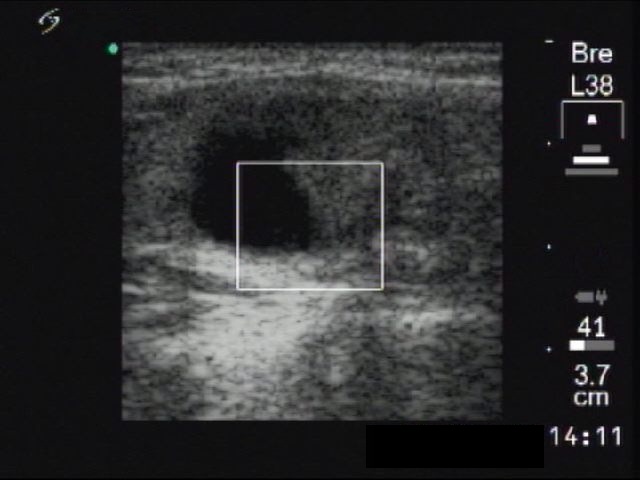

Ultrasonography: There was a mixed, cystic, moderately hypoechogenic nodule with microcalcification in the left thyroid. The lesion was avascular on Doppler mode.